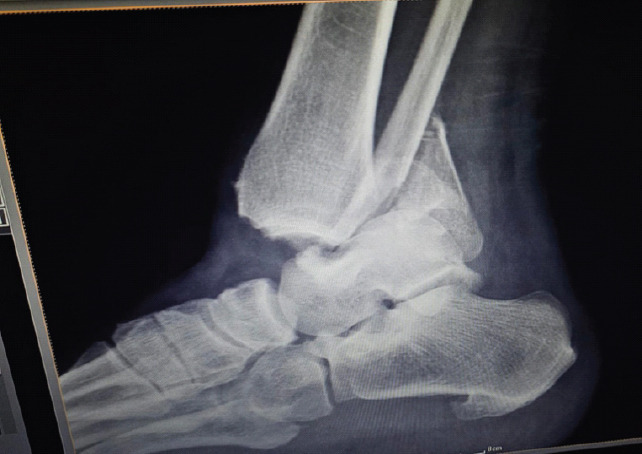

Case report: A 65-year-old female was involved in a car accident and suffered a Grade IIIA open trimalleolar fracture-dislocation. Radiographs confirmed the syndesmotic disruption and posterior talar subluxation. She underwent emergency surgery that included open reduction and internal fixation of the medial and lateral malleoli, as well as the use of an ankle-spanning external fixator. Her surgical recovery went smoothly, with fast union and functional mobility restored.